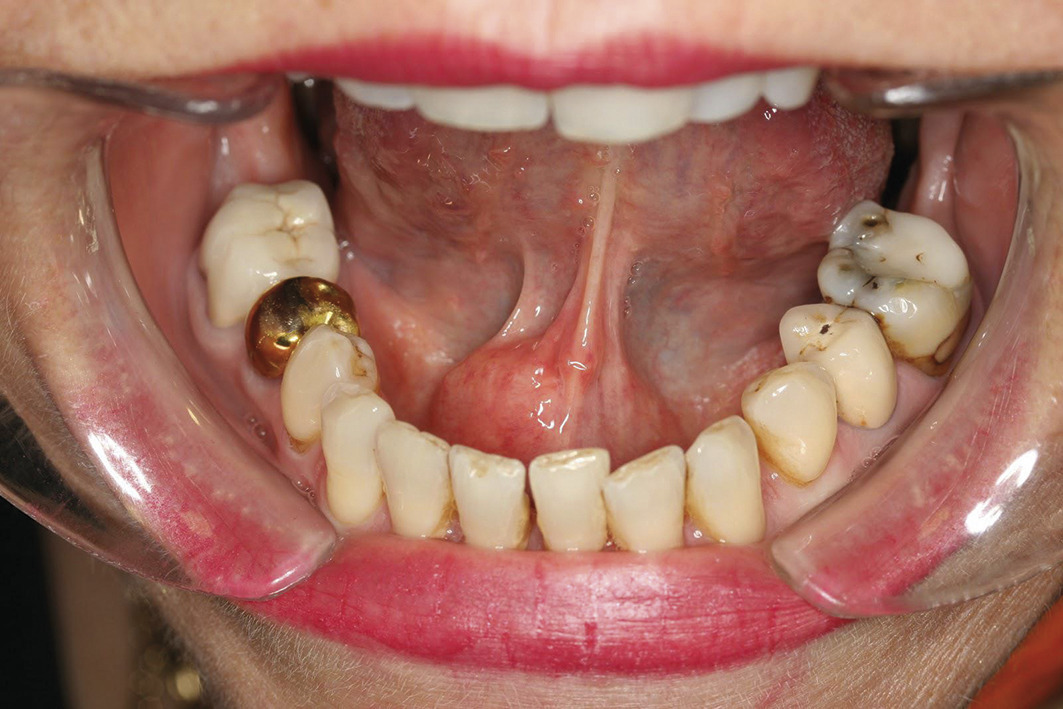

L’examen clinique avec palpation bidigitale (ou bimanuelle) permettra alors de retrouver le calcul dans le conduit submandibulaire (fig. 3 et 4).

Examen physique

L’inspection exobuccale recherche un gonflement de la glande. L’inspection endobuccale recherche une crête salivaire inflammatoire, une issue de salive ou de pus à l’ostium.

La palpation de la glande confirme le gonflement, alors que la palpation bidigitale de la glande et du conduit pratiquée d’arrière en avant (pour éviter de repousser un calcul vers le hile) recherche un calcul.